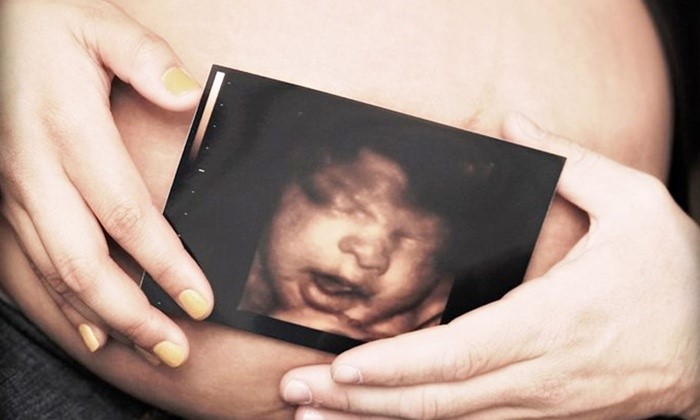

O ultrassom 3D é excelente para as mamães ansiosas. Com ele é possível ver o rostinho do bebê com detalhes em três dimensões.

Diferente do ultrassom comum, que só revela os ossos e órgãos internos do bebê, o ultrassom 3d é capaz de capturar a pele que cobre o bebê em suas imagens.

As imagens são capazes de revelar até o que pequeno está fazendo no momento do exame, em alguns é possível ver o bocejo ou uma linguinha de fora. E o melhor, dá para saber se o bebê vai parecer mais com a mamãe ou com o papai!

Estes tipos de ultra são eficazes para revelar mais detalhes de uma possível anormalidade. (Foto: Groupon)

Para ter a oportunidade de conhecer seu bebê antes do nascimento talvez será preciso pagar à parte pelo ultrassom 3D, que possui o valor não tão acessível assim. Para obter o melhor resultado no exame, é indicado o período entre 26 e 30 semanas de gestação para fazê-lo, pois nas semanas anteriores o bebê ainda não possui muito tecido adiposo sob a pele, o que dificulta na captura das imagens.